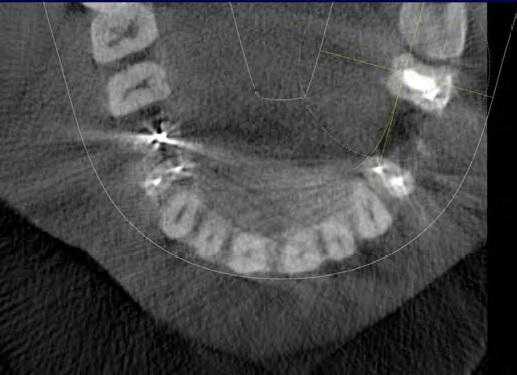

Ramamurthy и Matherene описывают ограниченность 2D изображений для определения MB2 каналов (Фото 1).

Фото 1: изображение MB2 в обоих первых молярах

Baratto Filho исследовали внутреннюю морфологию удаленных первых моляров верхней челюсти, сравнивая с данными, полученными при осмотре в микроскоп и при получении изображений КЛКТ ex vivo. Отчеты показали наличие 4-х каналов в 67,14% зубов и дополнительные корневые каналы в 92,85 % случаев в мезиобуккальном корне. Клиническая оценка показала слегка сниженный общий показатель (53,26%), но повышенный показатель выявления MB2 (95,63%), в то время как применение КЛКТ показало 37,05%. Ученые сделали вывод, что КЛКТ является хорошим методом для начальной оценки внутренней морфологии первого верхнего моляр, но для выявления устьев самым оптимальным способом является применение микроскопа. КЛКТ также применялся для выявления высокой встречаемости дистолингвального канала у Тайванцев, выявления аномалий в системе корневых каналов нижних премоляров, и помощи в выявлении искривлении корня (Фото 2).

Фото 2: Аксиальное изображение каналов C-формы во вторых молярах